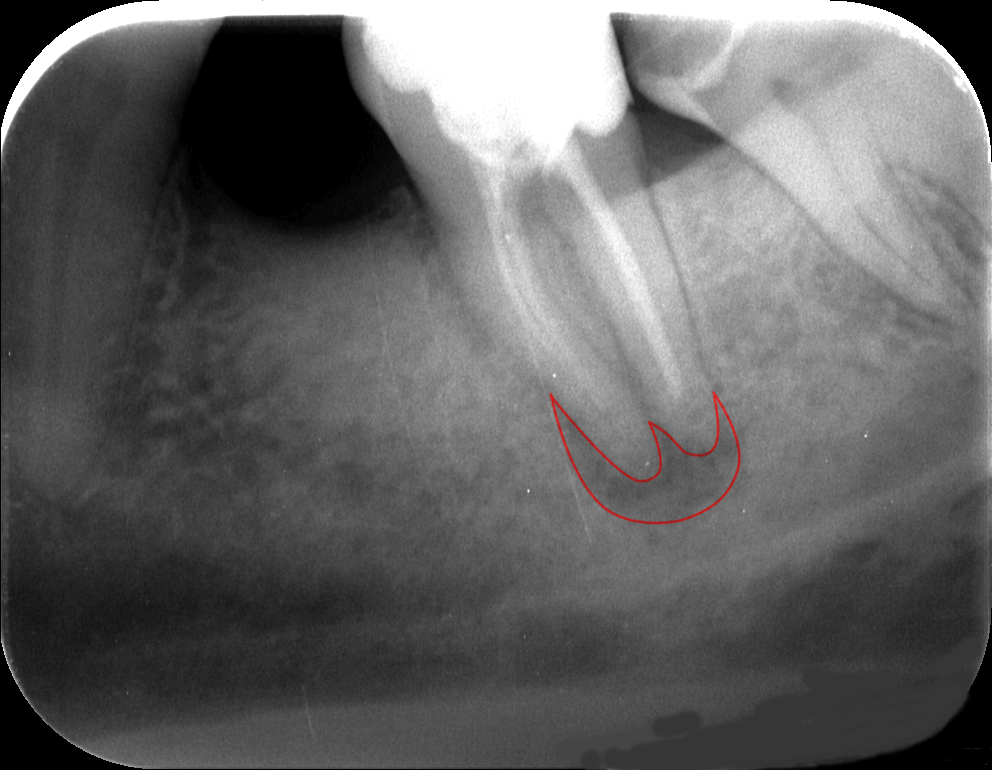

A lenti felvételen például, amely egy gyökérkezelés előtt készült, a pirossal körberajzolt terület gyulladásban van.